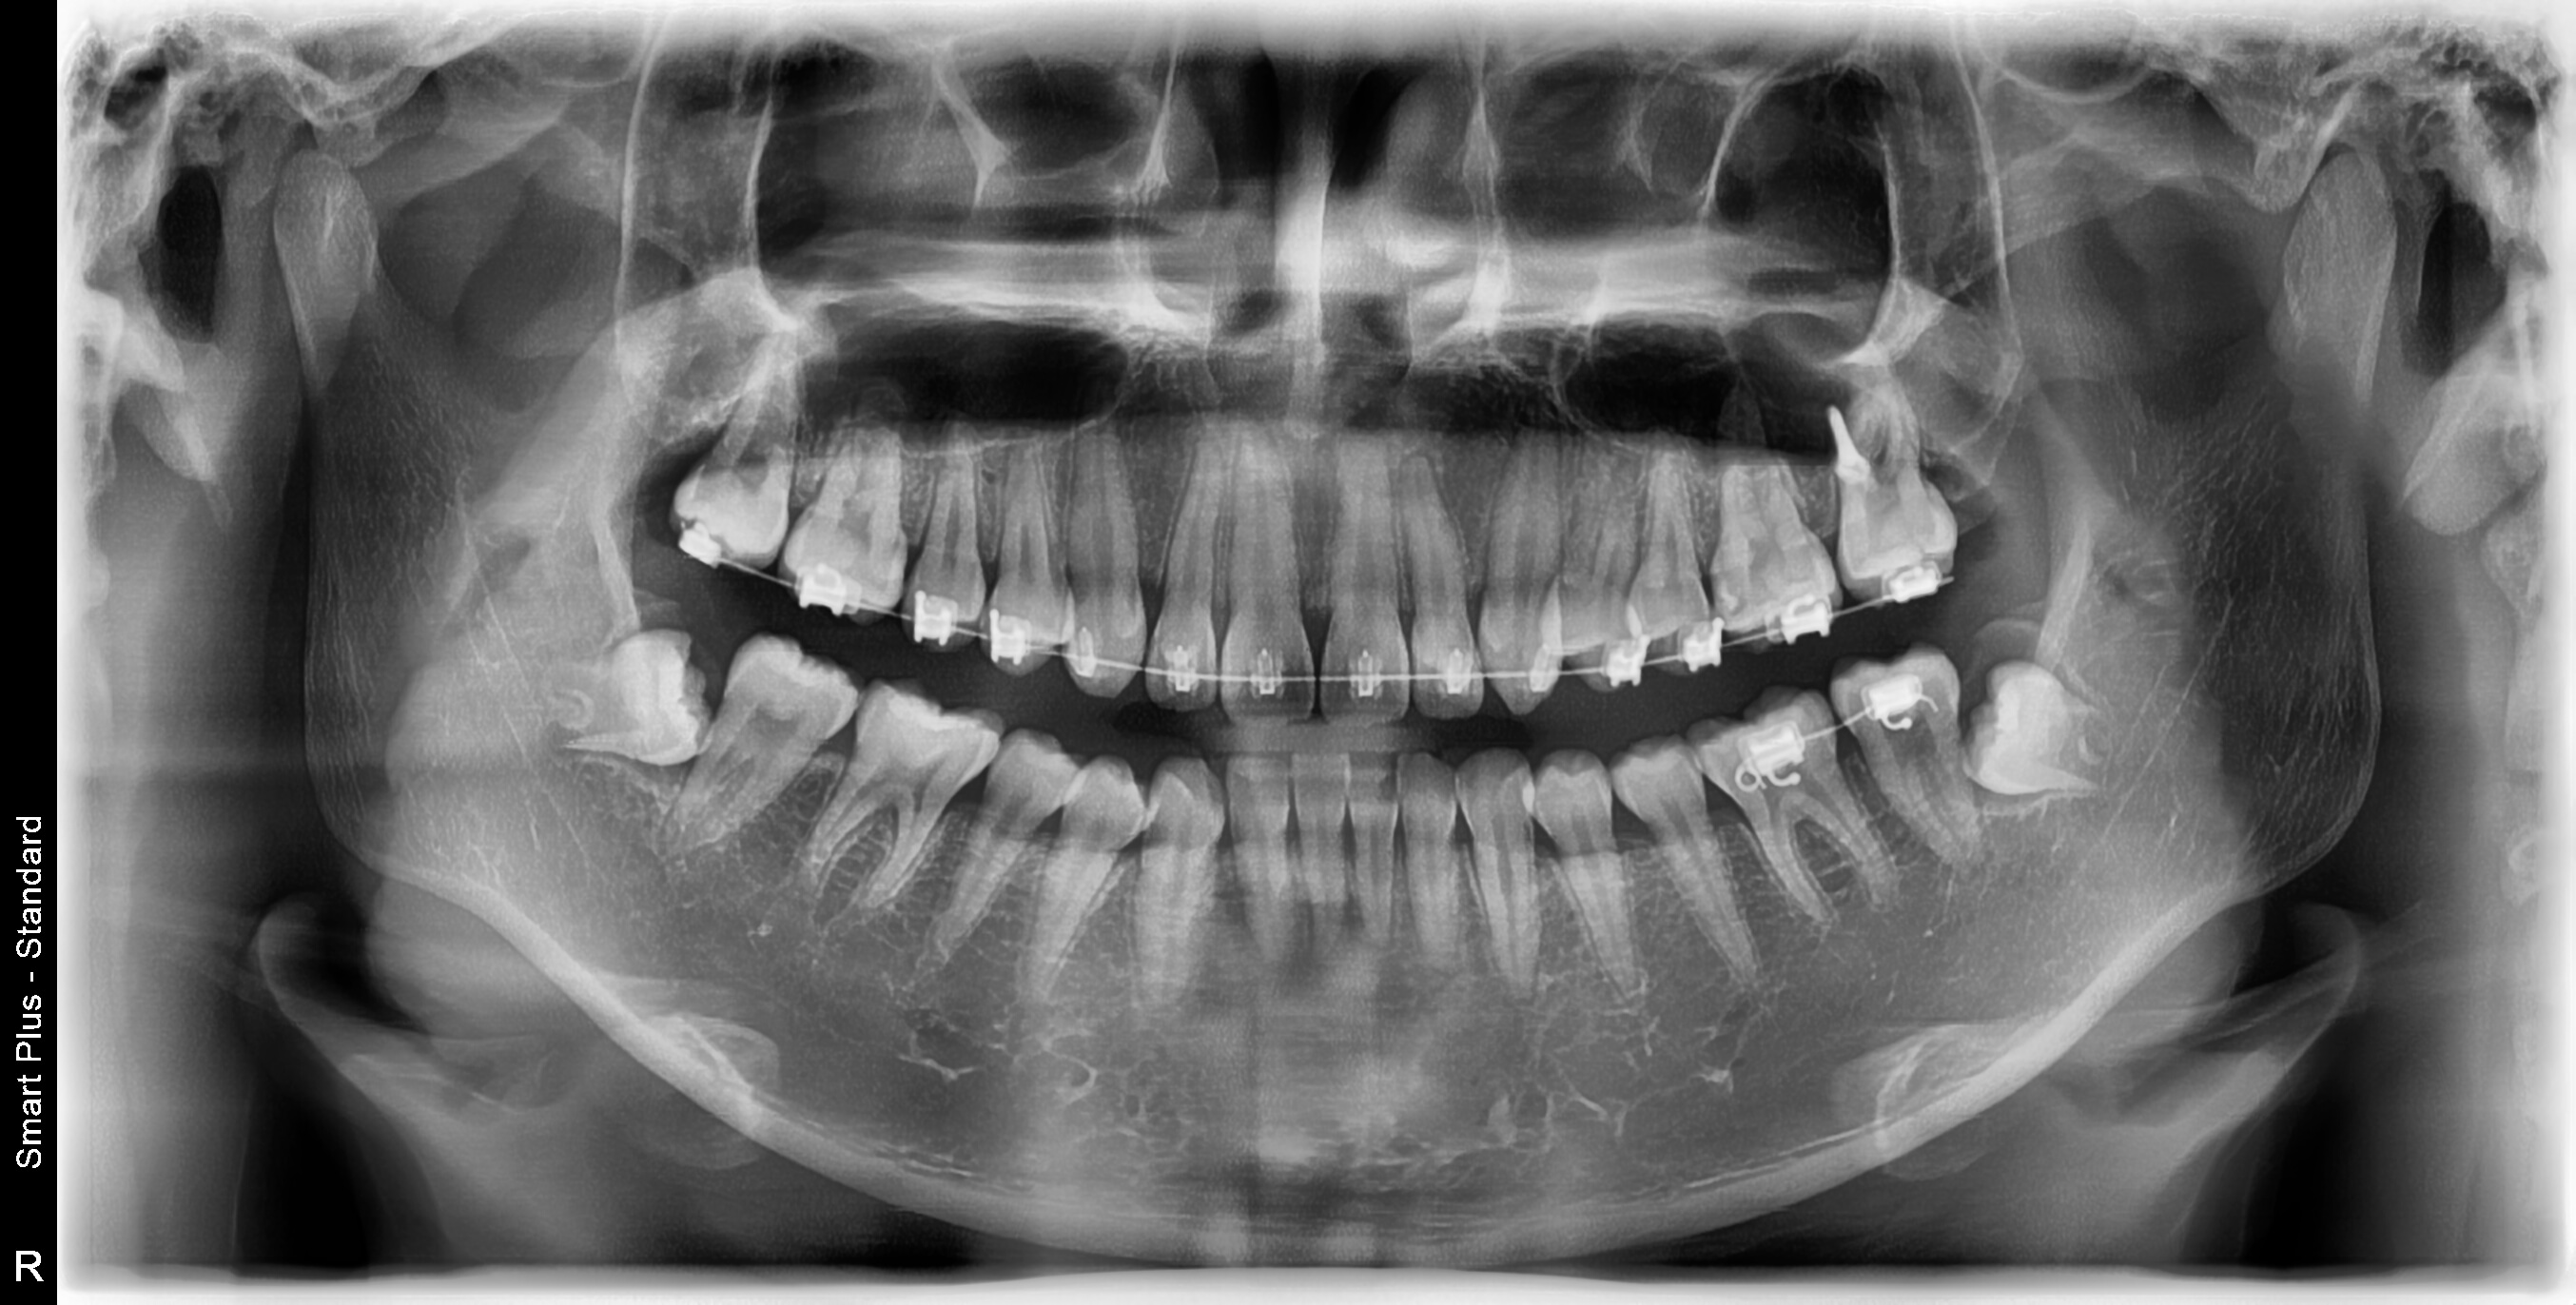

전체적인 치아상태 및 배열 안면윤곽 상태 등 정밀검사를 실시하였으며 아들이 고등학생이어서 성장판 검사는 별도로 하지 않았습니다.

정밀검사비용은 150,000원이 들었으며 전체교정비용은 590만 원으로 결정이 되었습니다. 치료방법에 따라 다르기 때문에 참고만 하시길 바랍니다.

● 검사결과 내용

치아뿌리상태는 좋고 어금니 가위교합(3개월정도)을 먼저 하고 어느 정도 진행이 되면 전체브라켓을 설치 후 과개교합(2개월정도) 교정을 실시한후 2차 정밀검사를 하고 발치여부를 판단하기로 하였습니다.

저는 상담 시 되도록이면 발치는 하지 않는 방향으로 한다고 말씀드렸고 다행히 2차 정밀검사 마친 후 발치 없이 전체교정을 시작할 수 있었습니다.

▼ 1차 정밀 검사 X-RAY

▼ 치아상태 및 얼굴 각도 치아 치수확인